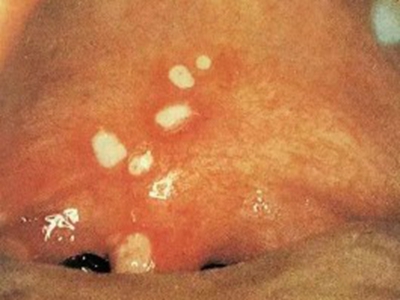

疱疹性咽峡炎典型体征为咽部充血,口腔黏膜出现数个灰白色丘疱疹或小水疱,直径1-2mm,周围绕以红晕,2-3日后,红晕加剧并扩大,疱疹破溃形成溃疡,表面覆有假膜白色或淡黄色,一般一周左右愈合。